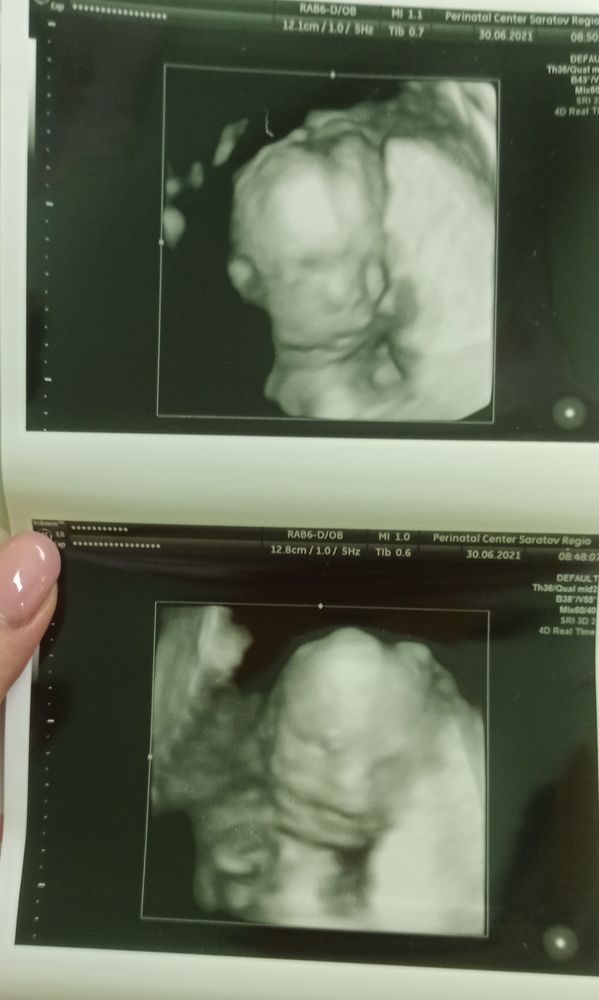

Мой сыночек! Сегодня был очень волнительный день, день второго скрининга. Слава Богу с малышом всё в порядке, всё органы на своих местах и развиваются как надо. Это просто чудо, сынуля на экране махал мне ручкой и угрожал кулачком. С 19 недели он стал очень активным, пиночки всё ощутимее. Старший сын очень счастлив что-то него будет брат! Девочки, делаю всем испытать это счастье. Удачи всем нам.